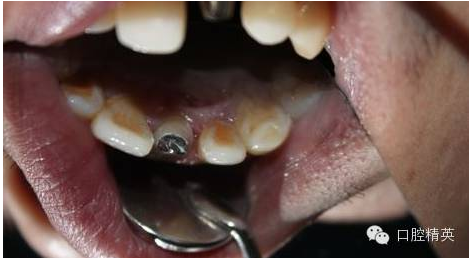

3:鈷鉻金屬樁黏結(jié)后

4:舌面觀,

5:頜面觀,排齦,待黏冠